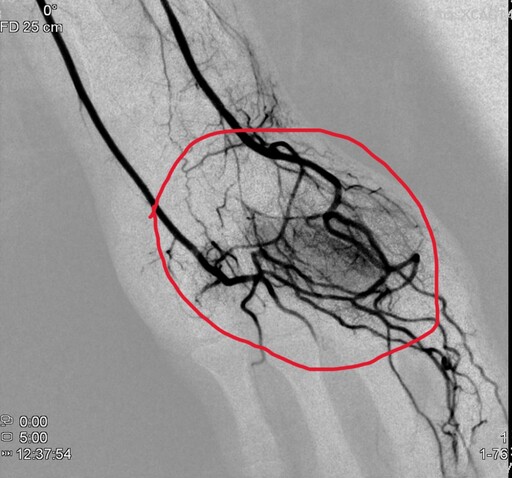

▲因職業傷害無法工作的廚師,經員榮醫院心臟內科主任林彤宥醫師在X光透視下導引微導管,將栓塞劑注入異常增生血管。(員榮醫療提供)

負責手術的林彤宥主任解釋,療程與心導管、腫瘤栓塞相似,從手腕橈動脈或鼠蹊部股動脈進行穿刺,在X光導引下將栓塞材料注入異常血管,使周邊神經因血流受阻而降低活性,疼痛訊號因而減少。「原本影像上呈現雲霧狀的血管,栓塞後馬上變得清晰許多,疼痛也跟著減輕。」林主任說。

因職業傷害無法工作的廚師,右手新生的異常微細血管(圖左,標注為B),處理過程中異常微細血管逐漸消失(圖中),手術過異常微細血管都被不見(圖右,標注為A)